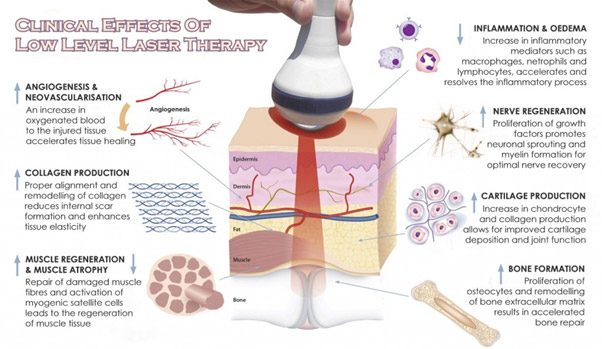

Clinical Effects of Low Level Laser Therapy

Anti-Inflammatory Action— Laser light reduces swelling caused by bruising or inflammation of joints to give enhanced joint mobility.

Stimulated Nerve Function— Slow recovery of nerve function in damaged tissue can result in “dead” limbs or numb areas. Laser light speeds the process of nerve cell reconnection to bring back motor and sensory innervation.

Pain Relief-Decreased inflammation and increased nerve function will inhibit both acute and chronic pain.

Increased Vascular Activity— Laser light induces temporary vasodilation increasing blood flow to damaged areas.

Faster Wound Healing— Laser light stimulates fibroblast development and accelerates collagen synthesis in damaged tissue.

Rapid Cell Growth— Laser light accelerates cellular reproduction and growth.

Increased Metabolic Activity— Higher outputs of specific enzymes, greater oxygen and food particle loads for blood cells and thus greater production of the basic food source for cells, Adenosine Tri-Phosphate (ATP).

Reduced Fibrous Tissue Formation— Laser light reduces the formation of scar tissue following tissue damage from cuts, scratches, burns or post-surgery.